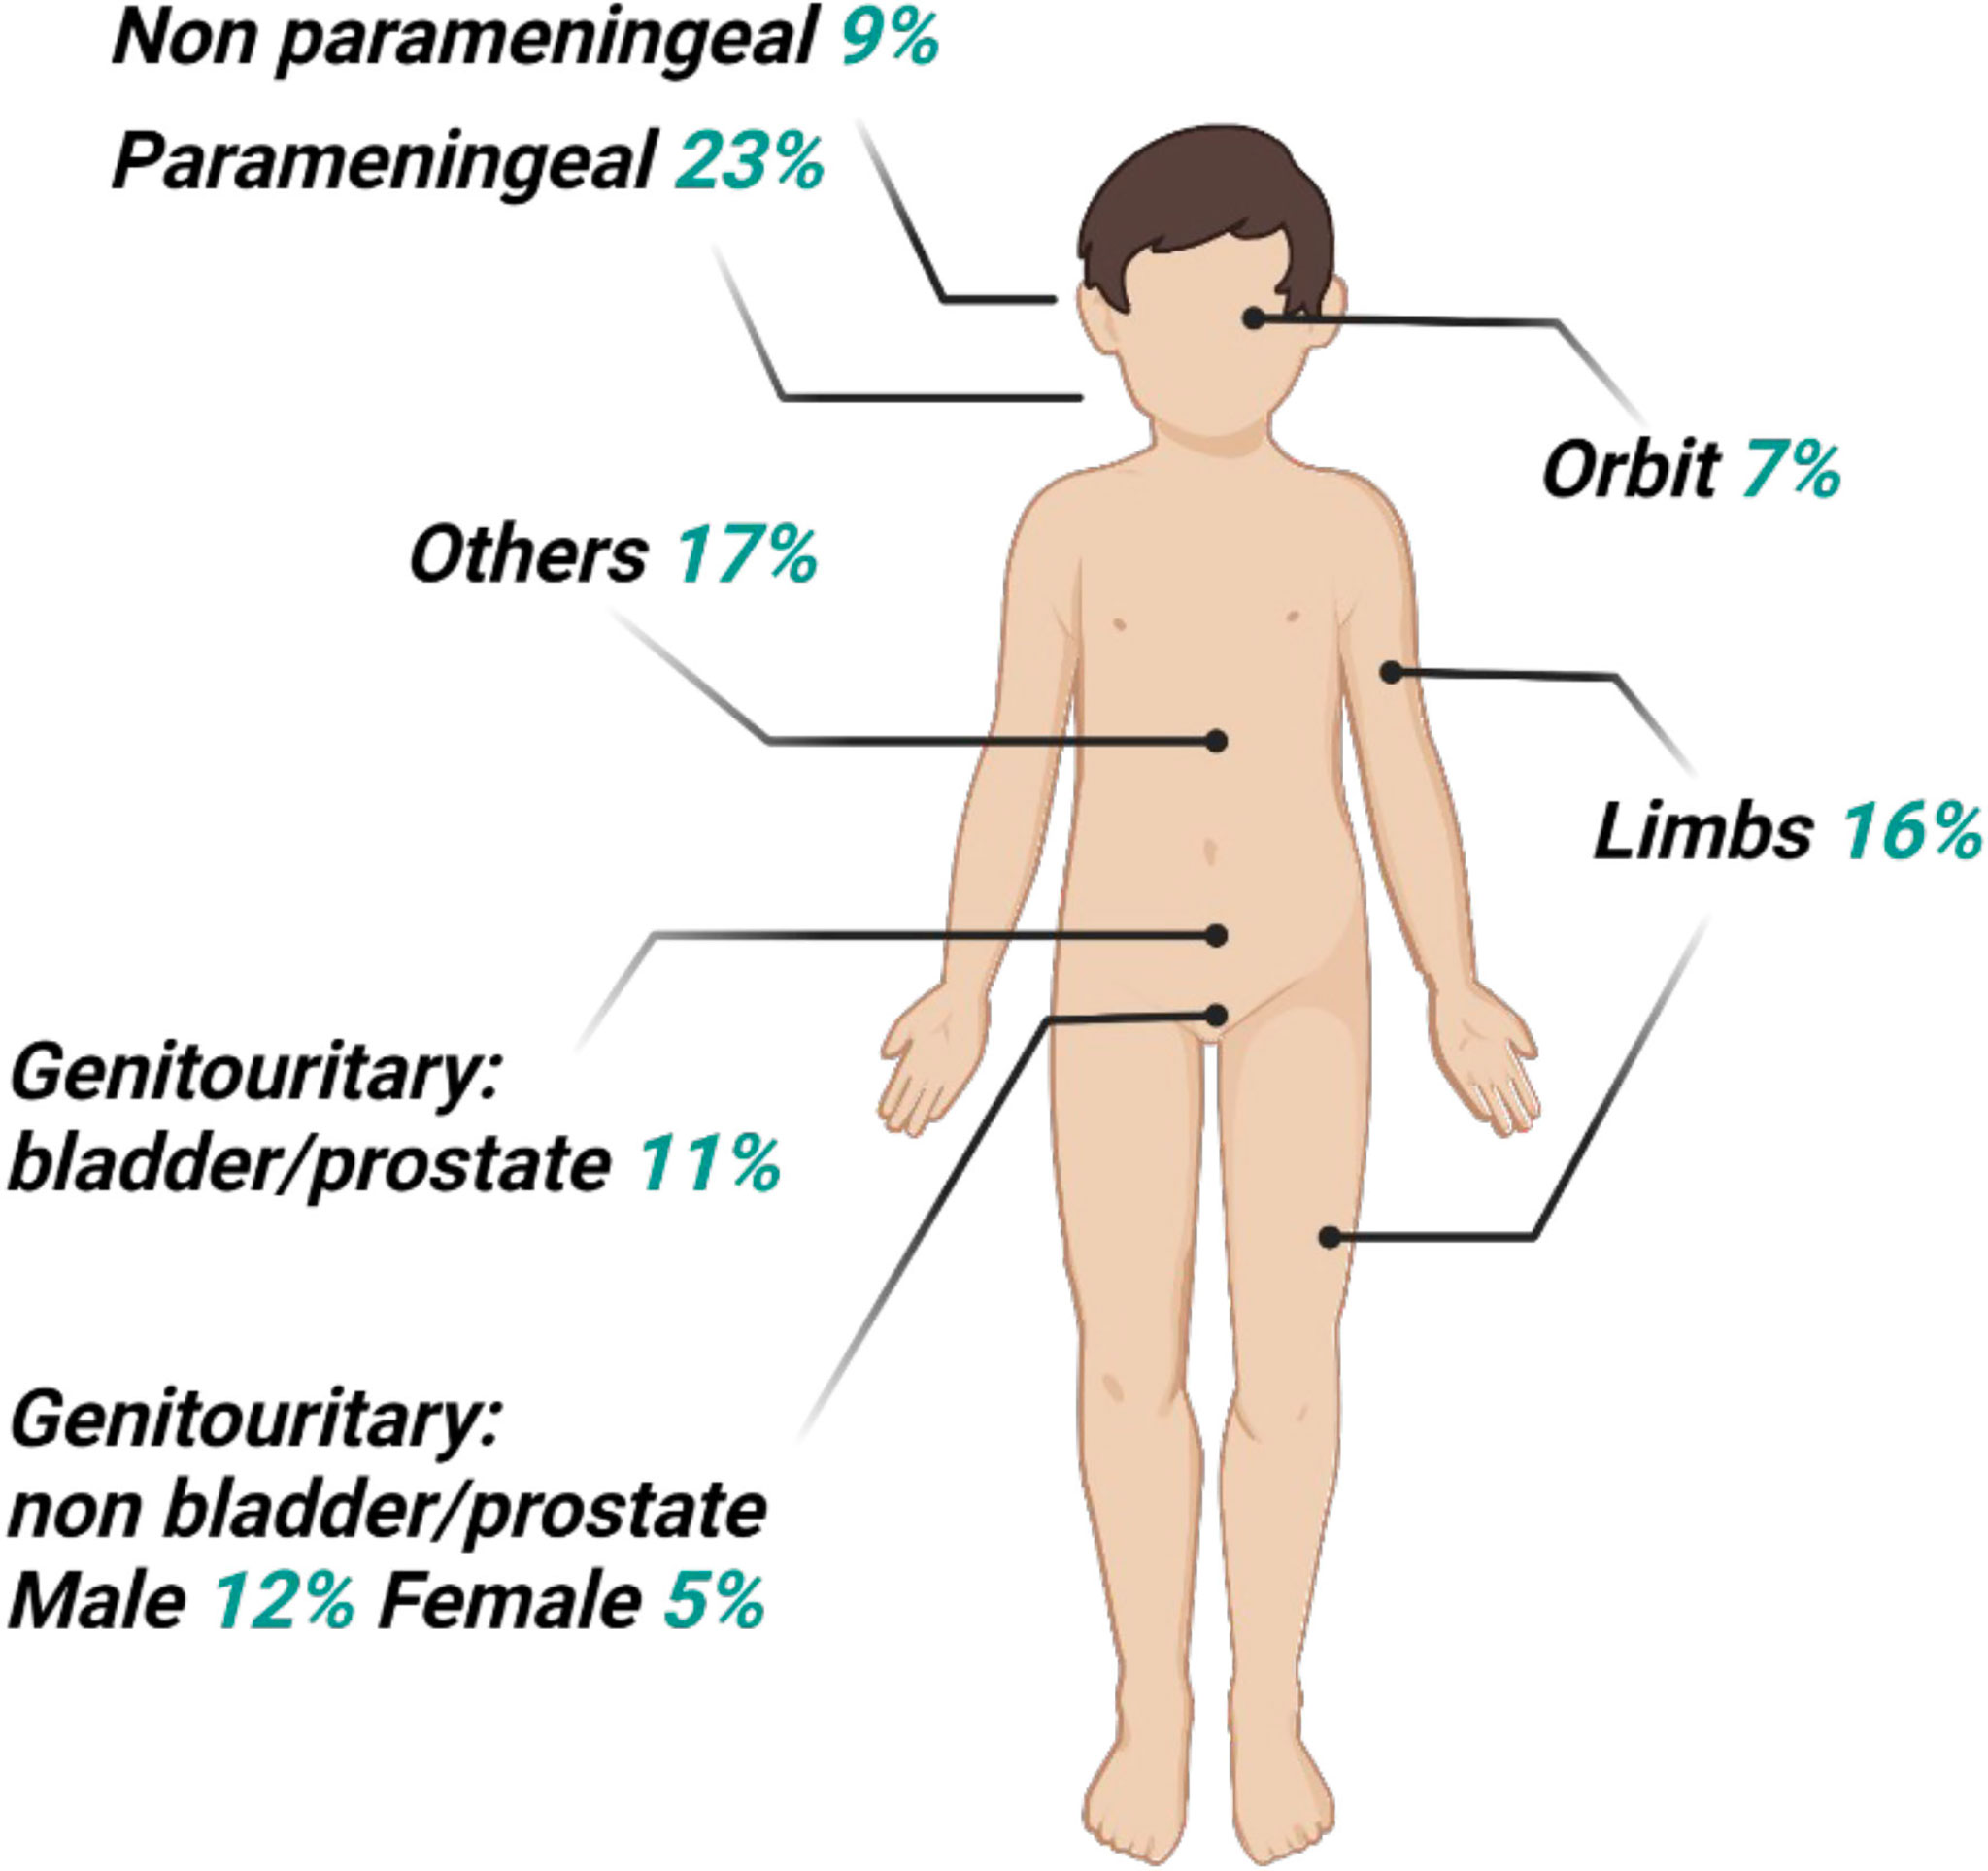

Frontiers | Radioresistance In Rhabdomyosarcomas: Much More Than A

www.frontiersin.org

www.frontiersin.org